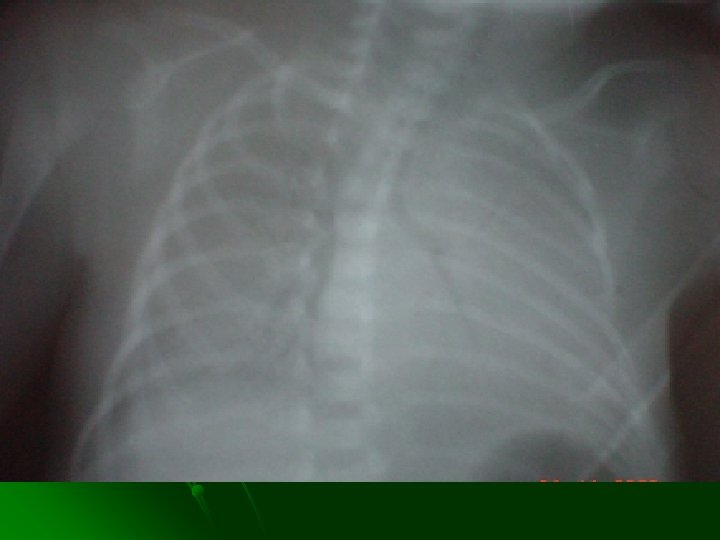

DIAGNOSTICO Radiología: l Disminución del volumen pulmonar. l Opacidad difusa reticulonodular “vidrio esmerilado”. l Broncograma aéreo. Resultado de la atelectasia alveolar y edema pulmonar. l Neumotórax y las otras formas de escapes aéreos.

IMAGENOLOGIA CLINICA LEVE MODERADO GRAVE MUY GRAVE ESTADIO I II IV Imagen reticulo nodular Muy fino localizado Todo el campo pulmonar Nodulos confluentes No se observa Broncograma Muy discreto Visible Muy visible Total Imagen Cardio tímica conservada Alterada por broncograma Muy alterada No se observa Transparencia pulmonar Conservada Disminuida Muy disminuida Opacidad total

SURFACTANTE Criterios de aplicación (primera dosis): l Edad menor a 24 horas de vida. l Radiografía de tórax compatible con enfermedad de membrana hialina. l Necesidad de asistencia ventilatoria fase III con FIO 2 > 40 % para lograr una Pa. O 2 > 50 mm. Hg. l Catéter arterial (umbilical o arterioclisis) para monitorización gasométrica y monitor de saturación transcutánea de oxigeno. l R a/A < 0. 22.

SURFACTANTE Criterios de reaplicación (dosis subsecuentes) Las dosis siguientes se administran cada 6 horas, si cumple los siguientes criterios: l Ventilación mecánica, con FIO 2 > 40% para mantener Pa. O 2 > 50 % l Presión media de la vía aérea ≥ 6 l Radiografía de tórax sin barotrauma, con datos de SDR, verificando la adecuada posición de la cánula endotraqueal. l Se recomienda administrar no más de dosis subsecuentes